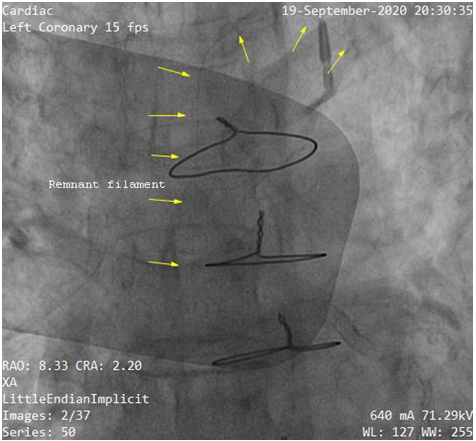

Subsequently, we made several attempts using simple manoeuvers like traction, pull and push without success. Unfortunately the guide wire was fractured and entrapped leaving part in LCX and LM (Figure 2). The patient suddenly complained of severe chest pain. The blood pressure went down to 70/50mmHg. The fluoroscopic test injection show severe LM (Figure 3) and left circumflex (LCX) artery dissection (Figure 4). Due to rapid hemodynamic destabilization, Subsequently, LM stenting with 3.5x18mm Biomatrix Alpha drug eluting stent (Biosensors, Shangdong, China) was performed (Figure 5). Another Biomatrix Alpha (Biosensors, Shangdong, China) drug eluting stent (DES) 2.75×18mm was successfully crossed with the broken guidewire and was deployed at LCX to sealed the fractured fragment to the vessel wall.The procedure result was excellent with Thrombolysis in Myocardial Infarction (TIMI) 3 flow distally (Figure 6). After the placement of the stents, an intra aortic balloon pump (IABP) was placed. The patient’s chest pain was resolved. The hemodynamic condition was improved but we later observed retained filaments in the ascending aorta (Figure 7 & 8). The patient declined surgical intervention for removal of these stray filaments and was discharged the following day with stable condition. During the subsequent monthly follow up visits, she was in a good condition and follow up with triple anti-platelet medication with no complications.

Figure 2 After deployment of the stents over the left circumflex artery (LCX), a fracture occurred at the LCX and left main (LM).

Figure 7 Retained filaments in ascending aorta.

Figure 8 Retained filaments in ascending aorta.